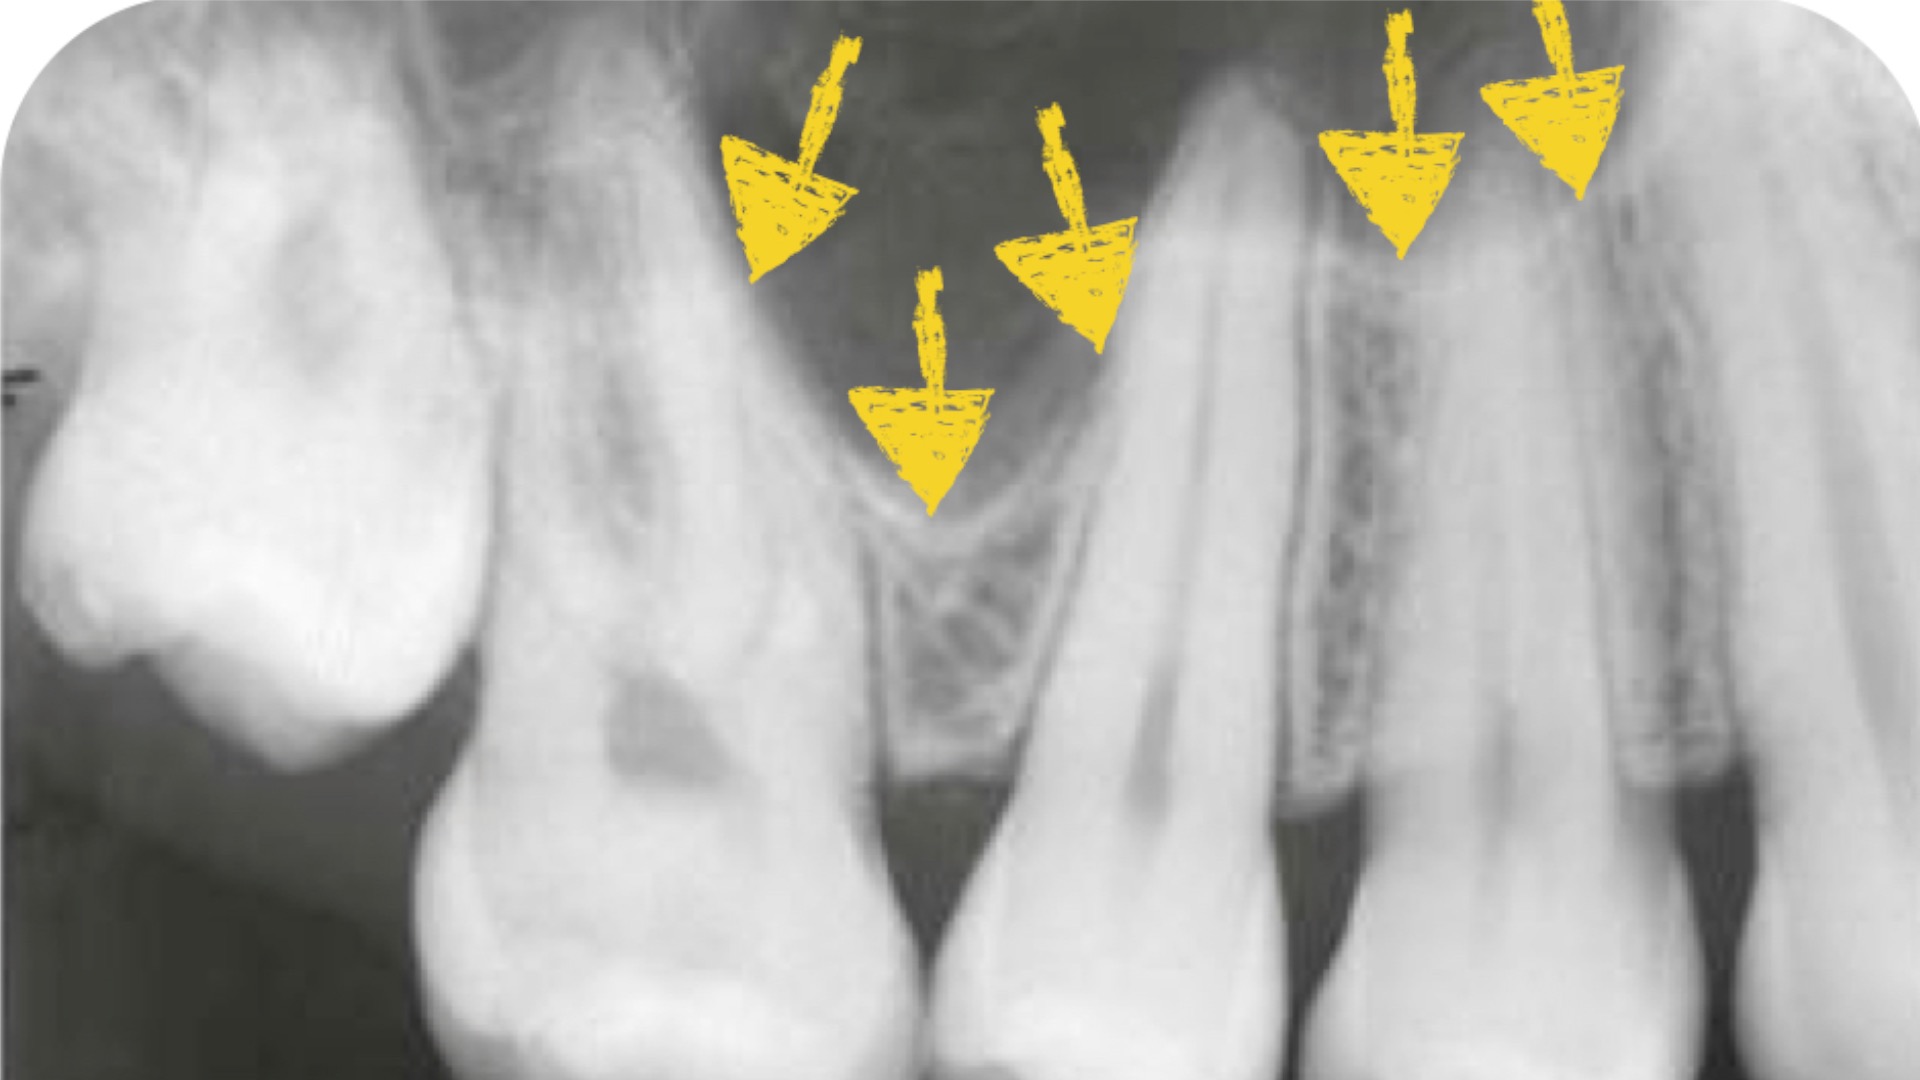

Tooth Extraction Hole To Sinus . signs of sinus infection after tooth extraction include red, swollen, and inflamed tissue around the perforation, with a discharge of. The first layer involves careful placement of collagen. sinus perforation is a complication that can occur during dental procedures like extractions or implant placements. when a root is lodged in the sinus cavity, it can lead to sinus perforation during the extraction, potentially causing infection or. how sinus perforation occurs during tooth extraction. if your sinus is perforated from tooth extraction, the tissue normally heals within four to six weeks. you could have very easily had a sinus perforation from the extraction of an upper tooth, and that would cause sinus. Bone grafting is often needed, though, and. Sinus perforation may occur during the removal of teeth from the upper jaw because.

Bone grafting is often needed, though, and. if your sinus is perforated from tooth extraction, the tissue normally heals within four to six weeks. when a root is lodged in the sinus cavity, it can lead to sinus perforation during the extraction, potentially causing infection or. signs of sinus infection after tooth extraction include red, swollen, and inflamed tissue around the perforation, with a discharge of. Sinus perforation may occur during the removal of teeth from the upper jaw because. sinus perforation is a complication that can occur during dental procedures like extractions or implant placements. how sinus perforation occurs during tooth extraction. you could have very easily had a sinus perforation from the extraction of an upper tooth, and that would cause sinus. The first layer involves careful placement of collagen.